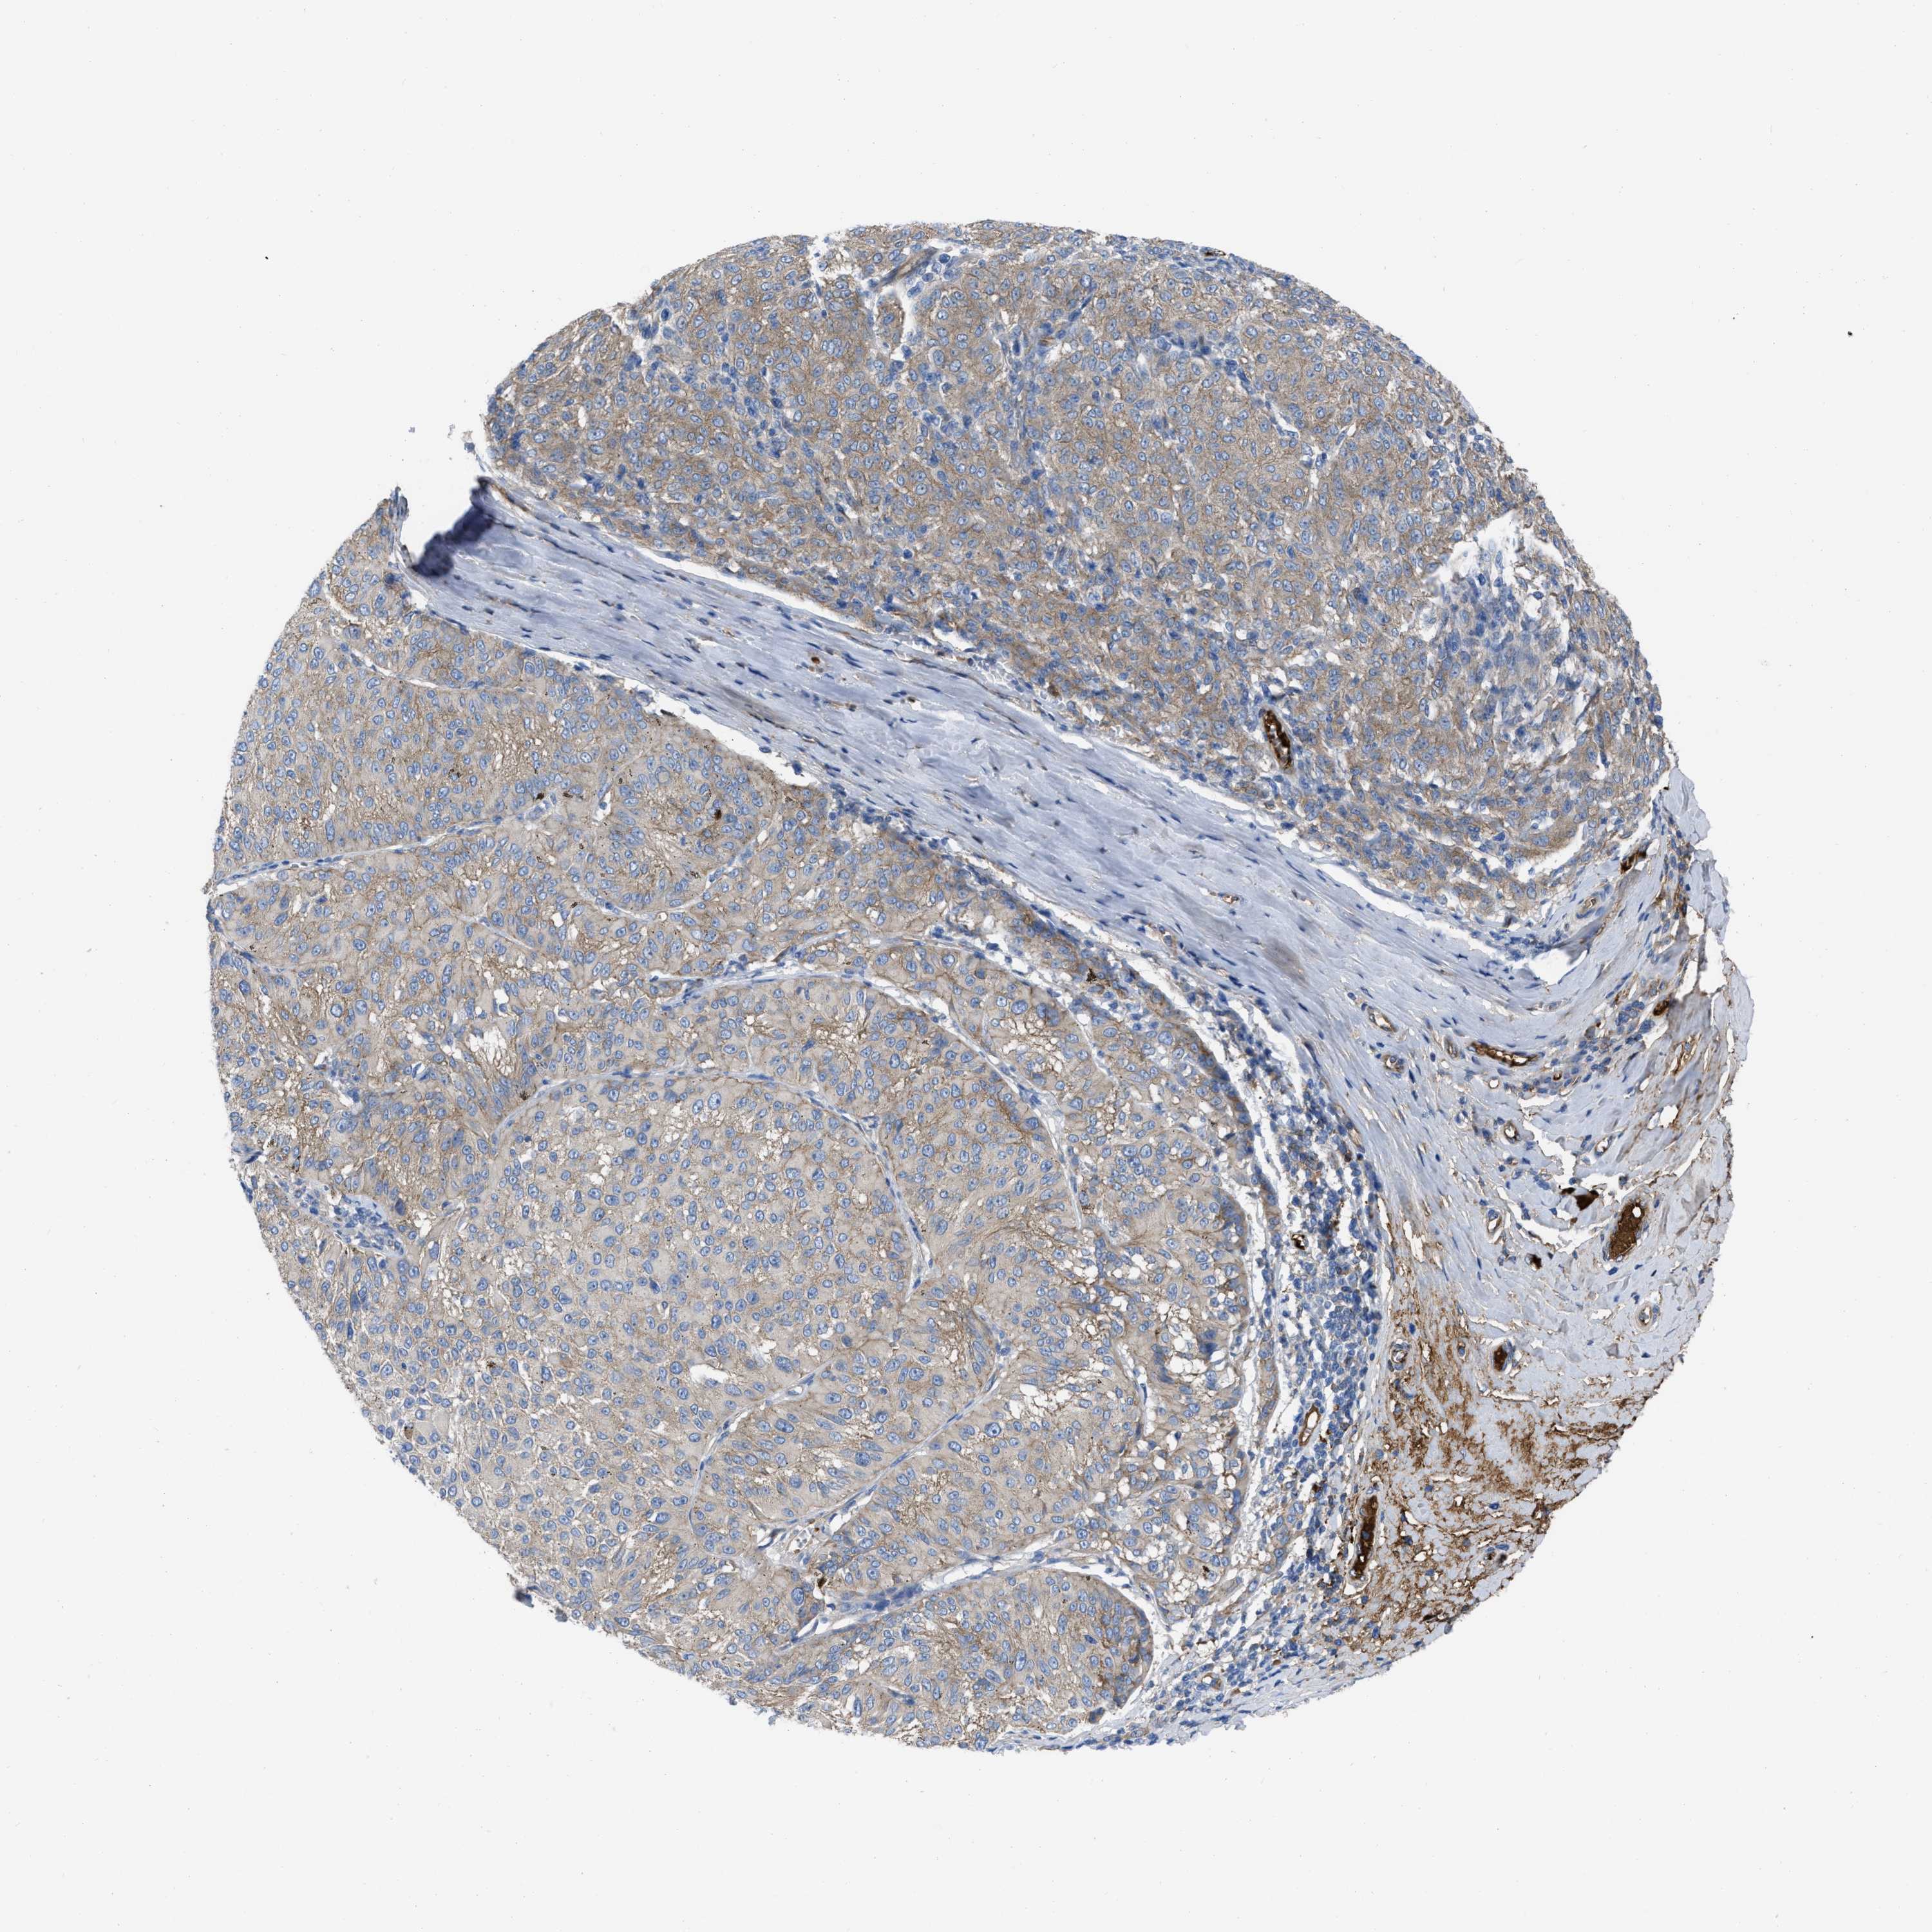

MELANOMA - Protein expressioni

A mouse-over function shows sample information and annotation data. Click on an image to view it in a full screen mode. Samples can be filtered based on level of antibody staining by selecting one or several of the following categories: high, medium, low and not detected. The assay and annotation is described here.

Note that samples used for immunohistochemistry by the Human Protein Atlas do not correspond to samples in the TCGA dataset.

Antibody stainingi

Antibody staining in the annotated cell types in the current human tissue is reported as not detected, low, medium, or high, based on conventional immunohistochemistry profiling in selected tissues. This score is based on the combination of the staining intensity and fraction of stained cells.

Each image is clickable and will lead to virtual microscopy that enables deeper exploration of all samples and also displays staining intensity scores, fraction scores and subcellular localization as well as patient and tissue information for each sample.

Antibody HPA003747

Antibody HPA019769

Staining

High

Medium

Low

Not detected

Intensity

Strong

Moderate

Weak

Negative

Quantity

>75%

75%-25%

<25%

None

Location

Nuclear

Cytoplasmic/membranous

Cytoplasmic/membranous,nuclear

Malignant melanoma, NOS

Malignant melanoma, Metastatic site